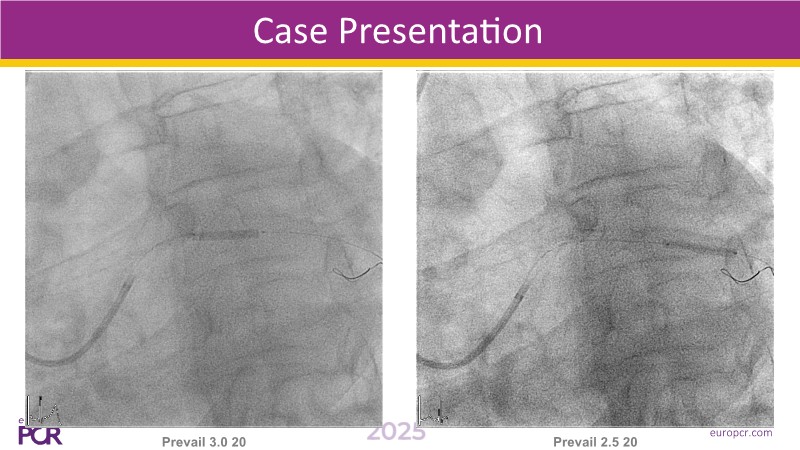

This EuroPCR 2025 session challenges the conventional approach to bifurcation PCI and dissection management. Learn why drug-coated balloons (DCB) may offer better long-term outcomes in cases where stents fall short, how DCBs can simplify bifurcation strategies, and why it’s time to rethink which dissections really need stenting. Through data, case examples, and clear decision-making insights, you'll gain the confidence to broaden your DCB practice where it truly matters.

- To analyse clinical data and use case of drug-coated balloons in bifurcation PCI